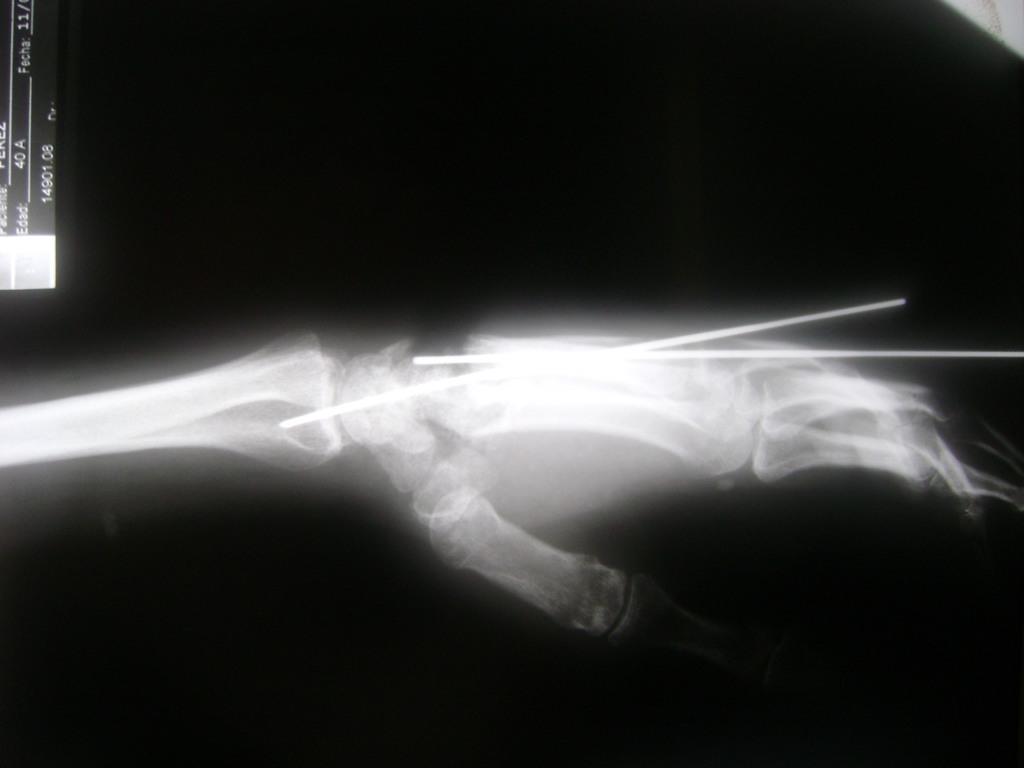

Cirugías de Calcaneo - Cirugías de Muñecas y Manos

Los procedimientos más comunes en cirugía de la mano son aquellos destinados a reparar traumatismos, incluyendo lesiones de tendones, nervios, vasos sanguíneos, y articulaciones; huesos fracturados; y quemaduras, cortes, y otros daños de la piel.